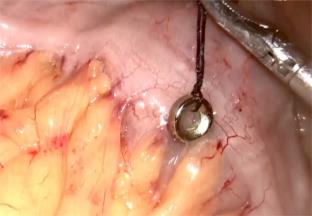

• 完全神经内镜下显微血管减压术联合神经梳理术治疗原发性三叉神经痛的临床疗效及其对预后的影响

摘要:目的 探究完全神经内镜下显微血管减压术(MVD)联合神经梳理术治疗原发性三叉神经痛(TN)的临床疗效及其及对预后的影响。方法 回顾性分析2021年11月-2023年11月该院收治的108例原发性TN患者的临床资料,根据不同手术方案,将患者分为联合组和对照组,各54例。对照组采用MVD治疗,联合组采用完全神经内镜下MVD联合神经梳理术治疗。比较两组患者总有效率、疼痛程度、应激指标、生活质量和并发症发生情况。结果 联合组总有效率为96.30%,明显高于对照组的83.33%,差异有统计学意义(P < 0.05);两组患者术后视觉模拟评分法(VAS)评分明显低于术前,且联合组明显低于对照组,差异均有统计学意义(P < 0.05);两组患者术后去甲肾上腺素(NE)、超氧化物歧化酶(SOD)和皮质醇(Cor)水平较术前明显升高,但联合组明显低于对照组,差异均有统计学意义(P < 0.05);两组患者术后生活质量综合评定问卷(GQOL-74)评分明显高于术前,且联合组高于对照组,差异均有统计学意义(P < 0.05);两组患者并发症总发生率比较,差异无统计学意义(P > 0.05)。结论 完全神经内镜下MVD联合神经梳理术治疗原发性TN,可减轻疼痛,减轻应激反应,提高患者生活质量。值得临床推广应用。